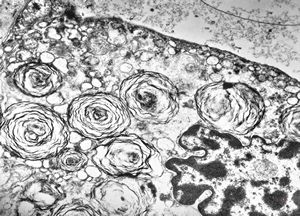

M,50y. | Pneumocystis carinii - lung